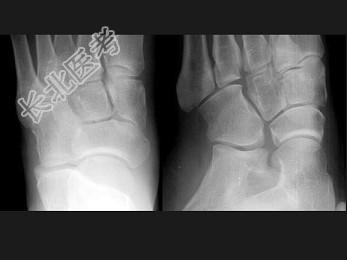

- 单项选择题女,25岁, 扭伤后足中部痛,结合图像, 最可能的诊断是 ( )

A、內侧楔状骨骨折

B、外侧楔状骨骨折

C、足舟骨骨折

D、中间楔状骨骨折

E、未见异常